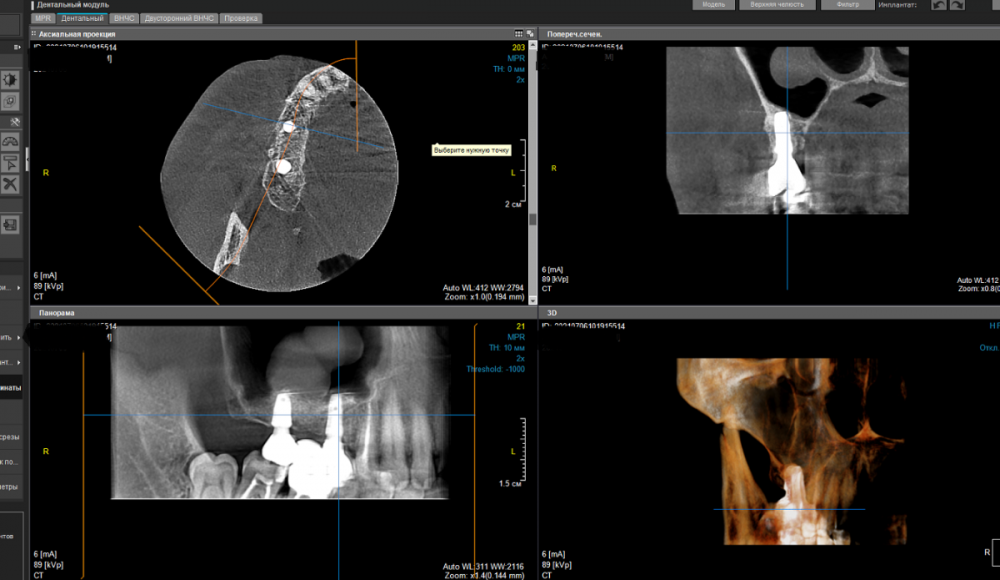

еатегsffhgj Опубликовано 6 июля, 2021 Автор Поделиться Опубликовано 6 июля, 2021 я сделал скрины. разные. Ссылка на комментарий

Irouil Опубликовано 16 июля, 2021 Поделиться Опубликовано 16 июля, 2021 Скорее всего речь идёт о костном остром крае, на одном из предоставленных срезов просматривается подобный контур гребня Если не беспокоит - не обязательно что-то делать, но можно превентивно сделать небольшой разрез и сошлифовать его Ссылка на комментарий